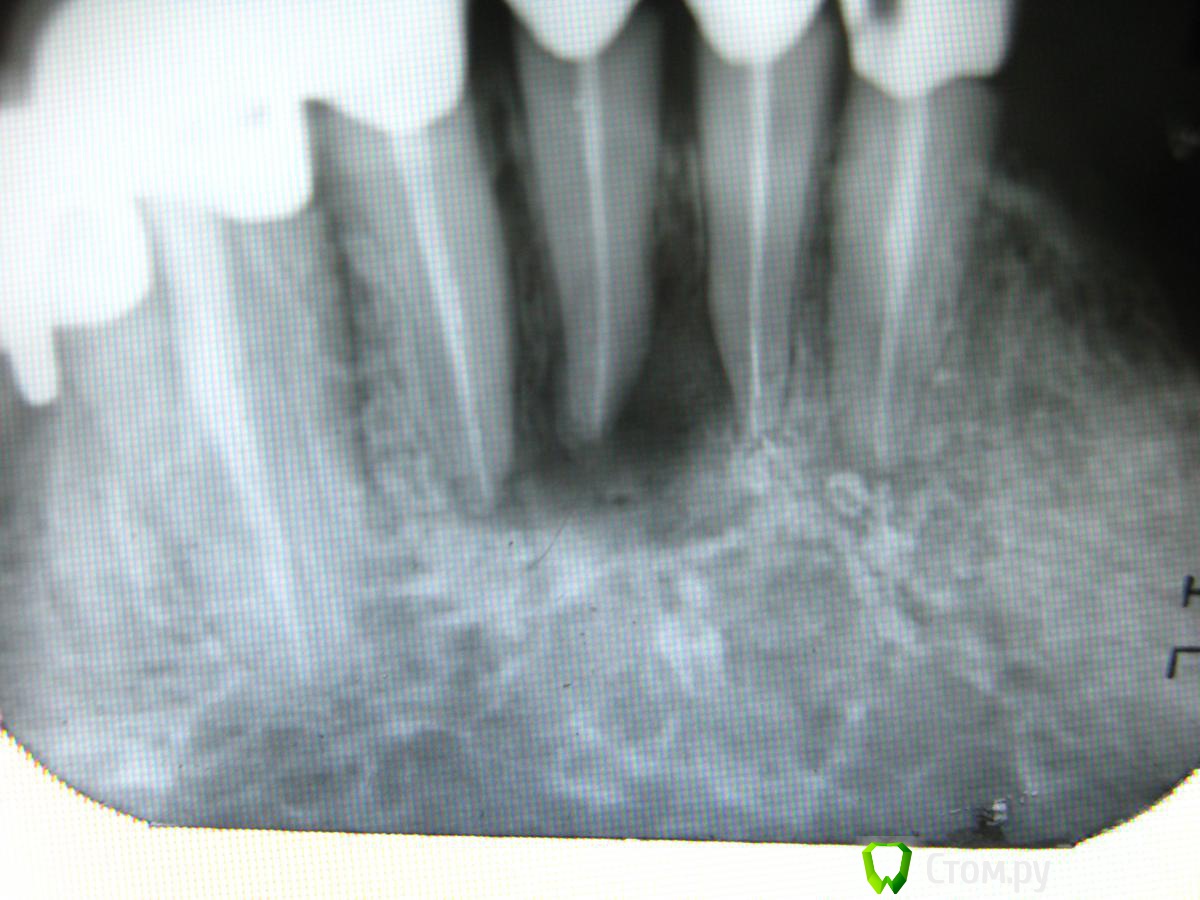

Abdul9848 Опубликовано 15 ноября, 2013 Поделиться Опубликовано 15 ноября, 2013 доброго времени суток, посоветуйте что можно сделать в данной ситуации Ссылка на комментарий

Kolchanov Опубликовано 15 ноября, 2013 Поделиться Опубликовано 15 ноября, 2013 Снять коронку, распломбировать, найти возможно пропущенный канал, его тоже обработать, все запломбировать, восстановить и снова коронку.Если болит, а надо сделать так, чтобы не болело, то порезать и антибиотики. Ссылка на комментарий

Shaid Опубликовано 15 ноября, 2013 Поделиться Опубликовано 15 ноября, 2013 Такое ощущение, что патология возникла вследствие нарушения коронального герметизма. Коронка как-то не плотно прилегает. Ссылка на комментарий

marffa Опубликовано 15 ноября, 2013 Поделиться Опубликовано 15 ноября, 2013 доброго времени суток, посоветуйте что можно сделать в данной ситуациираспломбировка, метапекс и под наблюдение с контролем Rg Ссылка на комментарий